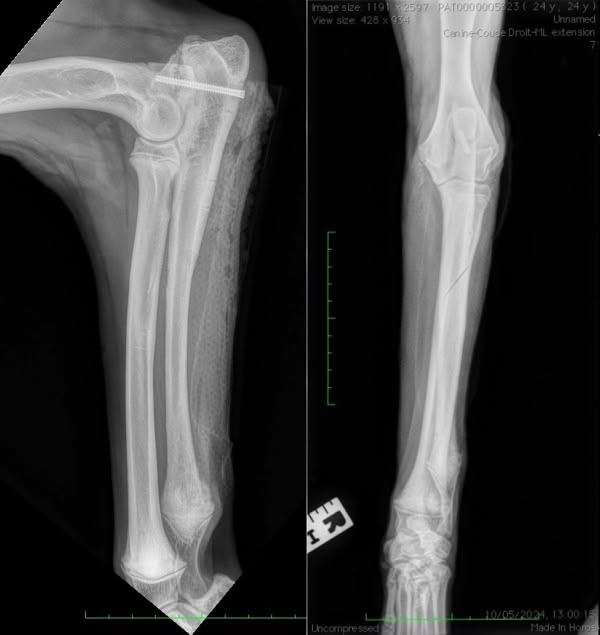

Figure 1

Figure 2